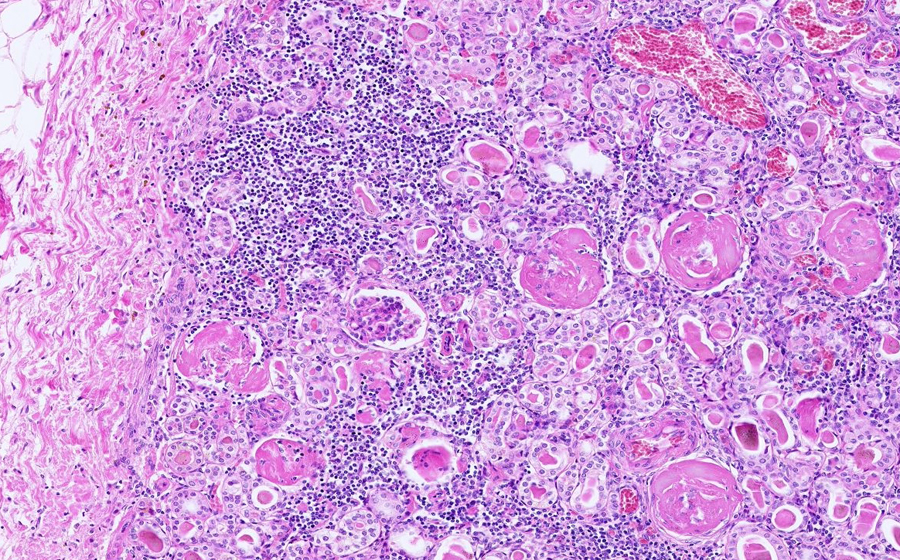

Slide 3: Glomerulonephritis - chronic

Histologic section of kidney from a patient with chronic glomerulonephritis. (click here to review normal tissue)

Image 1 - 6.3X